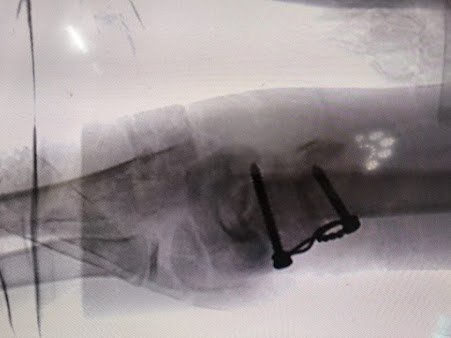

Hospital Gallery

The Veer Hospital is committed to providing affordable, quality health care to patients by incorporating improvement in its day-to-day schedule.